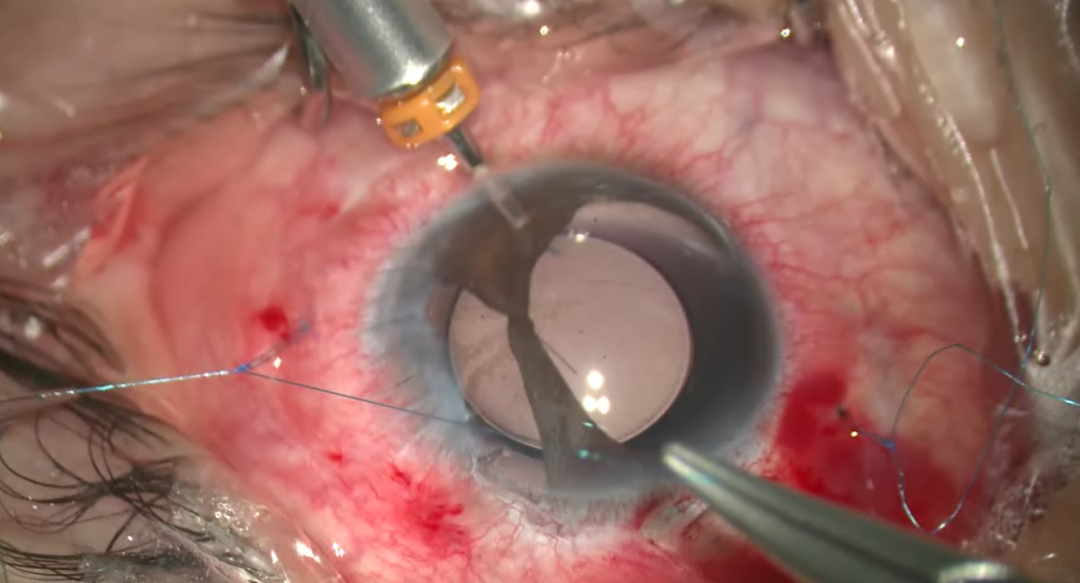

将8-0缝线置入27G针头针腔(suture-in-needle),距角巩膜缘1.5mm-2.0mm处进针,随后从主切口外置缝线环。推注IOL至露出一侧晶体襻,先用镊子持缝线环,以双线绕晶体襻一圈,随后将缝线环末端套至晶体襻上,最后收紧线结,即完成改良cow-hitch knot的制作(图1左示线环绕襻步骤,图1右示线环套襻步骤)。操作过程需要避免将IOL牵拉出推注器。

图1 改良cow-hitch knot的制作示意图,橙色:晶体襻;蓝色:位于襻下方的部分线;灰色:位于襻上方的部分线;绿色:位于蓝线下方的部分线;黄色:线环方向。